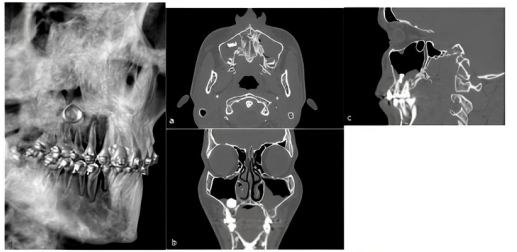

Homem, 18 anos, comparece ao serviço de cirurgia e traumatologia do hospital após

ter sido informado pelo seu ortodontista que havia um “corpo estranho” no seio maxilar direito. Ele

não relatava queixas inerentes à condição observada. Durante o exame clínico, o paciente relatou

que, há mais ou menos um ano, foi submetido à tentativa de extração do terceiro molar superior

direito sem sucesso, sem outras ou intercorrências no período. Ao exame físico extra e intraoral, não

foi observada nenhuma alteração digna de nota. Ao exame tomográfico, evidenciou-se uma área

hiperdensa na região referente ao seio maxilar direito com tamanho aproximado de 12 mm e

velamento deste, sugestivo da presença de conteúdo líquido a esclarecer em seu interior, e velamento

do seio contralateral.

Fonte: Agostinho, Santos e Araújo (2020).

Sobre presença de um corpo estranho no seio maxilar, analise as assertivas abaixo e assinale a alternativa correta.

IV. Os exames de imagem são imprescindíveis nesse caso e podem ser panorâmica, incidência de Waters, perfil de face e, sempre que possível, tomografia computadorizada.